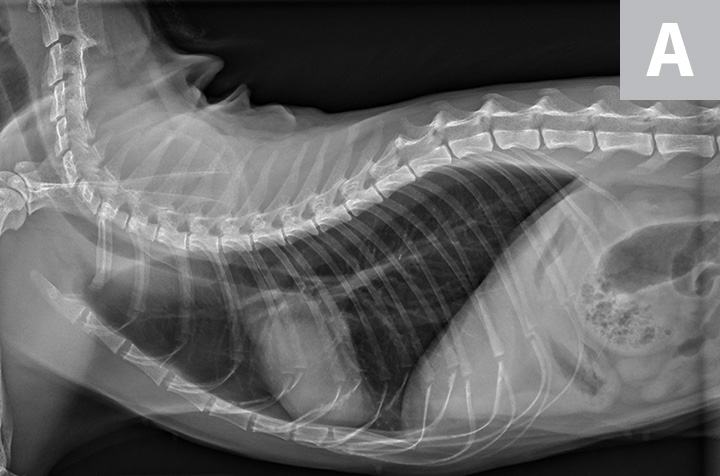

Learn How to Read a Cat X ray Long Beach Animal Hospital

Learn How to Read a Cat X ray Long Beach Animal Hospital